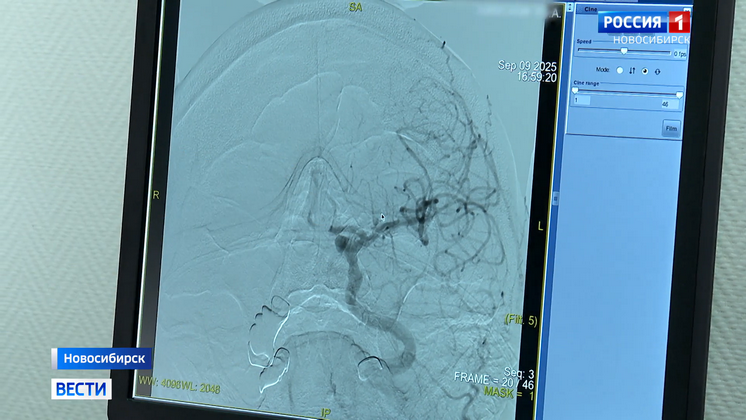

По скорой привезли в 34-ю больницу. Экстренно провели обследование: ишемический инсульт. Тромб закупорил одну из артерий головного мозга. Спасти может только высокотехнологичная операция — тромбоэкстракция — когда тромб через сосуды под рентген-контролем извлекают с помощью катетера.

На тот момент стационар уже получил все необходимое оборудование для таких вмешательств. Врачи прошли обучение. Лидия Тимофеева стала первым спасённым пациентом.

«Мы были готовы к этому несмотря на то, что первый раз делаем. Было волнительно, но расходные материалы, инструменты — всё есть. Прекрасная операционная, приняли решение и сделали», — отметил Руслан Ибрагимов, заведующий рентген-операционной городской клинической больницы № 34.